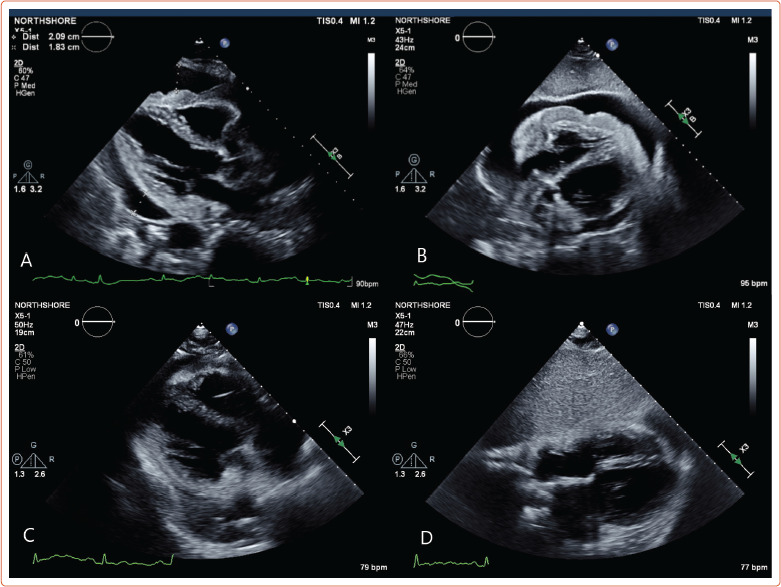

原发性心脏肿瘤仅占全部心脏肿瘤的0.3%;其中,淋巴瘤仅占所有原发性心脏肿瘤的2%。心脏淋巴瘤预后恶劣,由于诊断和治疗的延误,往往不到1年。心脏MRI是心脏肿瘤成像的金标准。我们描述了一个76岁的男性病例,没有明显的既往病史,他在心脏MRI上发现大量心包积液与心脏淋巴瘤一致,而组织诊断为原发性心脏弥漫性大b细胞淋巴瘤。本文回顾了心脏淋巴瘤的临床和影像学特点,并讨论了患者的治疗管理和副作用。

Primary cardiac tumors account for only 0.3% of all cardiac tumors; of these, lymphomas account for only 2% of all primary cardiac tumors. Cardiac lymphomas have a grim prognosis, often less than 1 year due to delays in diagnosis and treatment. Cardiac MRI is the gold standard for the imaging of cardiac tumors. We describe the case of a 76-year-old man with no significant past medical history who presented to the emergency department with a large pericardial effusion that was found to be consistent with cardiac lymphoma on cardiac MRI prior to tissue diagnosis of a primary cardiac diffuse large B-cell lymphoma. The clinical and radiological features of cardiac lymphoma are reviewed, and the therapeutic management and side-effects that the patient experienced are discussed.